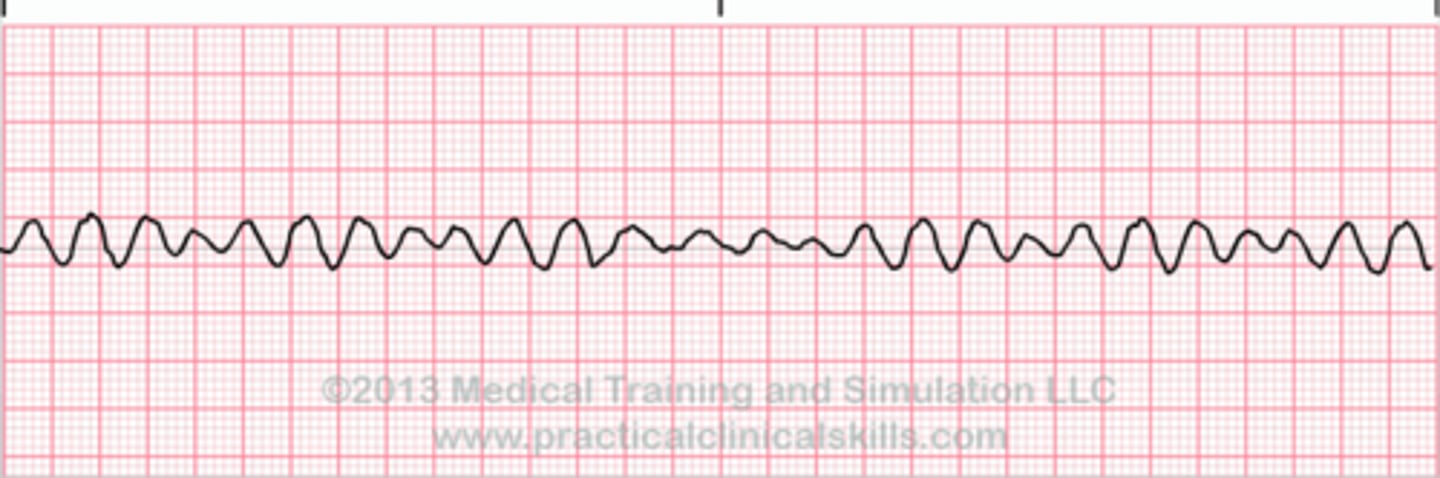

What is v fib?

you are dead, ventricles are quivering, clients have no pulse/BP/RR. fatal if not terminated in 3-5 minutes. Want Coarse v fib rather than fine because there is more of a rhythm to shock.

What is the treatment for v fib?

defibrillation immediately, CPR, epinephrine/vasopressin, O2, Amiodarone (V-FIB = D-FIB)